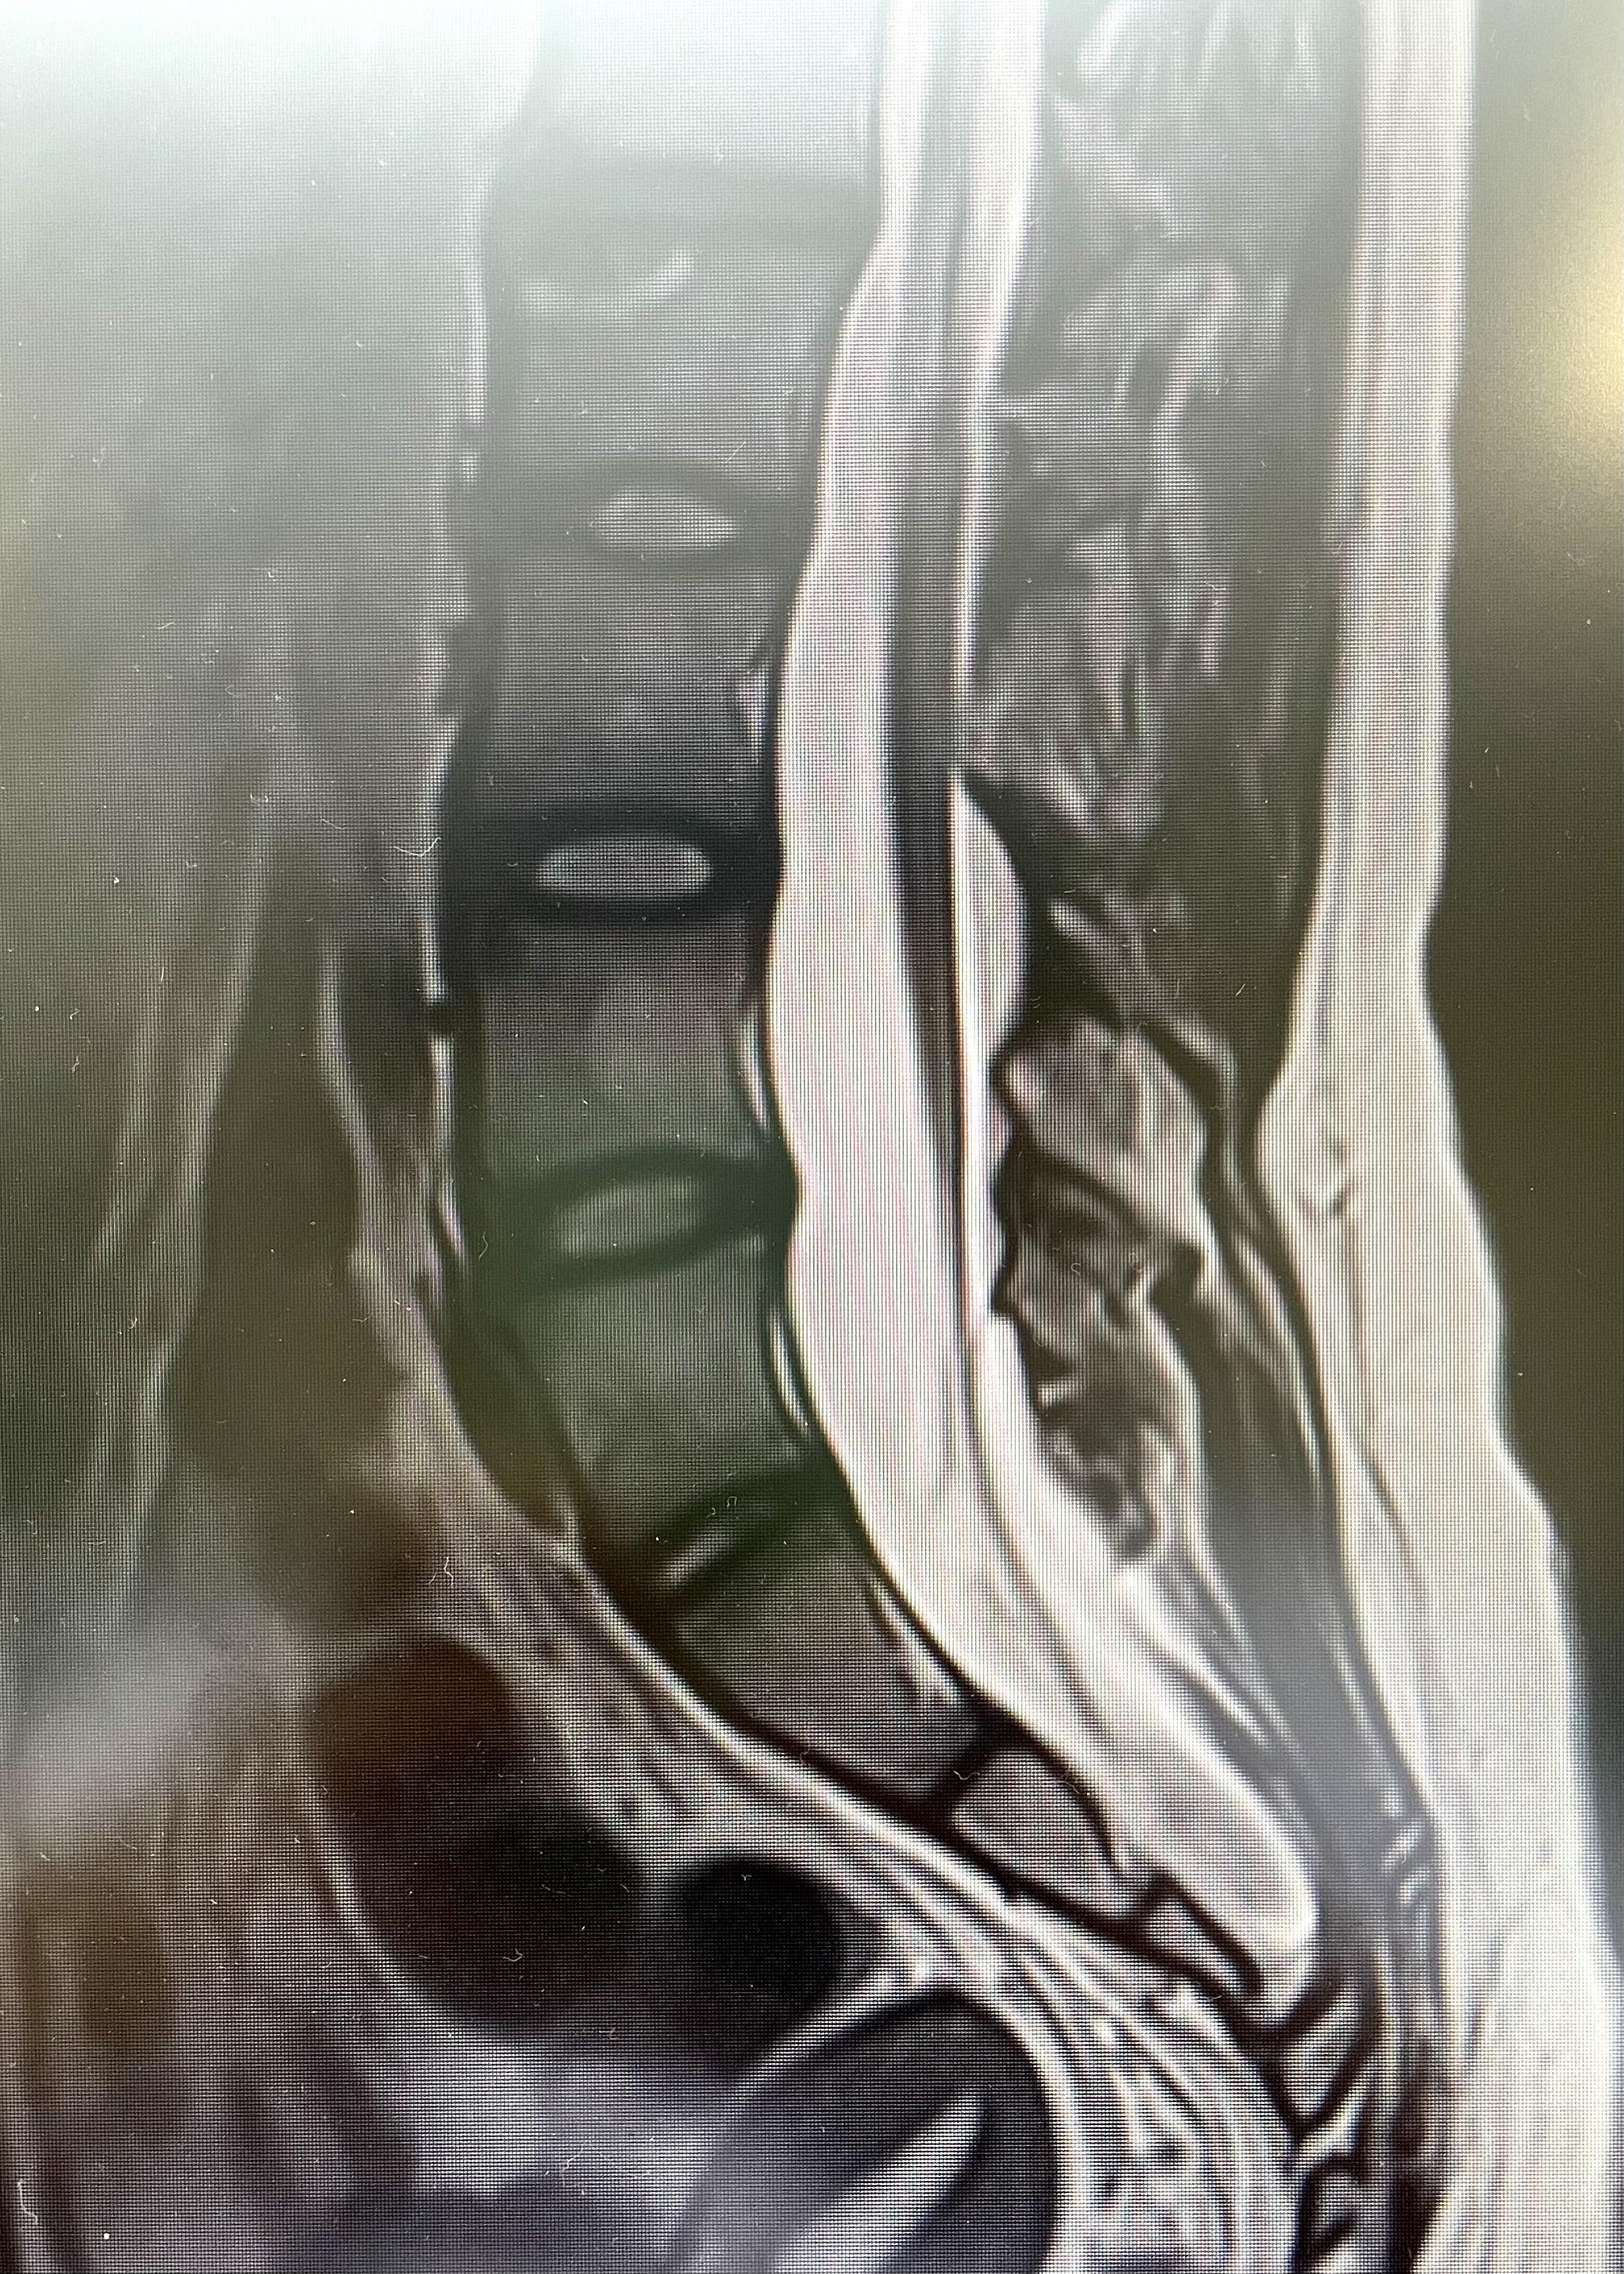

腰骶部MRI提示琳琳患脊髓拴系综合征

据接诊的王超主任医师介绍,琳琳患的疾病是脊髓拴系综合征,出现双足发育不等大,是由于琳琳的脊髓被长期“拴”住了,而最近脊髓被“拴”得愈发紧绷,导致琳琳双下肢疼痛的症状。